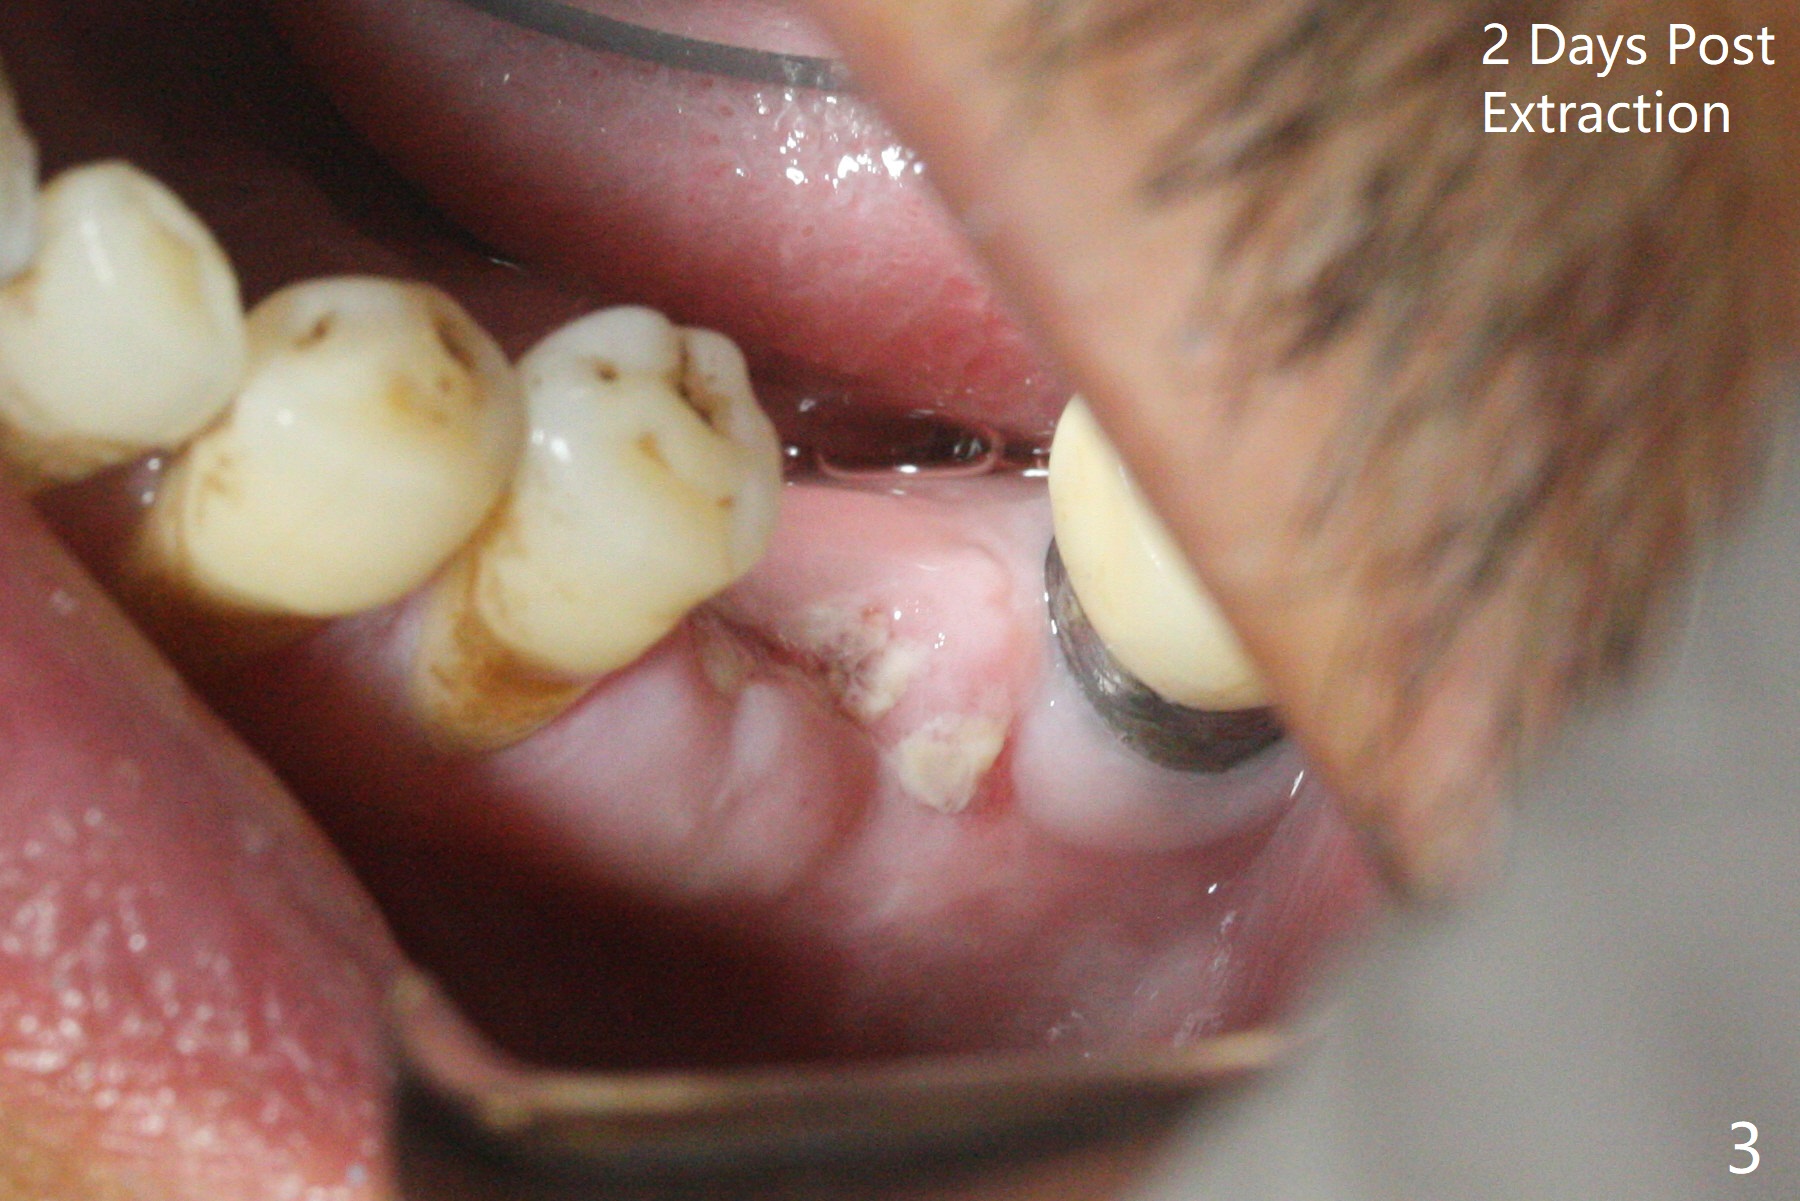

The 59-year-old man has so severe pain associated with #19 that he returns for extraction 2 days prior to guide arrival (Fig.1,2).拔牙后两天瘘道消失,牙槽窝口关闭(图三)。导板钻洞(4x7.3毫米)后,置入4x11毫米软组织水平植体,好像太短(图四),离神经(红虚线)3.5毫米。使用3.5x8.5毫米钻头后,植入4.5x9毫米骨水平植体,多次倒退,扭力35Ncm;马上安置基台(图五),然后粘性骨粉(图六:*)。